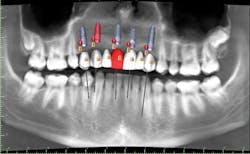

A cone beam computed tomography (CT) scan (Prexion 3-D cone beam unit, Prexion Inc.) of the upper jaw was obtained. A full-arch upper impression was taken in polyvinyl siloxane (PVS) and poured in model stone. Then a CT scan was taken of the model. Both sets of DICOM files were imported into Blue Sky Plan software (Blue Sky Bio LLC), where all digital planning occurred. Using the “add tooth” function, digital teeth were added into the DICOM files. These were overlaid on the digitized model, and all aspects (midline, horizontal plane, bite, and overjet) were checked using basic principles of implant restorability (figure 2). This was done to ensure proper placement for future implant workup. Based on the available bone, there was room for five implants (3.5 mm x 10.5 mm MegaGen AnyRidge implants): a single implant for No. 5 and implants in Nos. 6, 8, 9, and 11 for two three-unit bridges. Even though there was marked bone loss, angulations were adjusted as much as possible to allow for implants to emerge through the lingual of the incisor (figure 3). Once the correct orientation was complete, we designed a fully guided surgical kit to print one guide for all drills. Guides were exported as STL files and 3-D printed using an in-office CEL Robox 3-D printer out of nGen material (ColorFabb BV). After printing the guide, we added a metal sleeve housing (figure 4).

Figure 2: Digital workup in Blue Sky Plan software

Figure 3: Superimposed model overlaid with digital wax-up and meshed with cone beam computed tomography scan